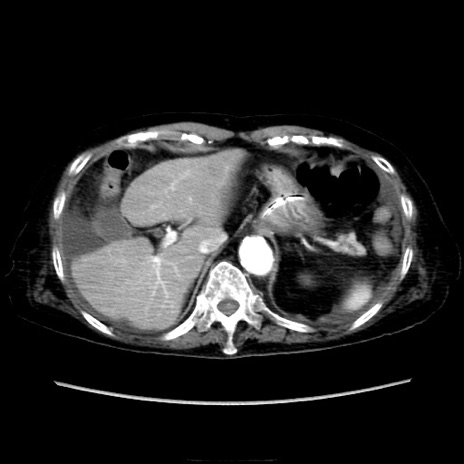

症例40(横断像)

【症例】90歳代女性

【主訴】腹痛・嘔吐

【現病歴】 食欲低下、嘔吐があり昨日他院受診。肺炎と診断され入院となる。入院後より腹部全体に圧痛あり。胃管留置され経過みていたが、症状持続するため、

当院転院となる。

【既往歴】胸椎圧迫骨折、胆石症

【身体所見】腹部:中央に激痛あり、圧痛あり、反跳痛不明

【データ】WBC 17100、CRP 18.82

他院CT

横断像